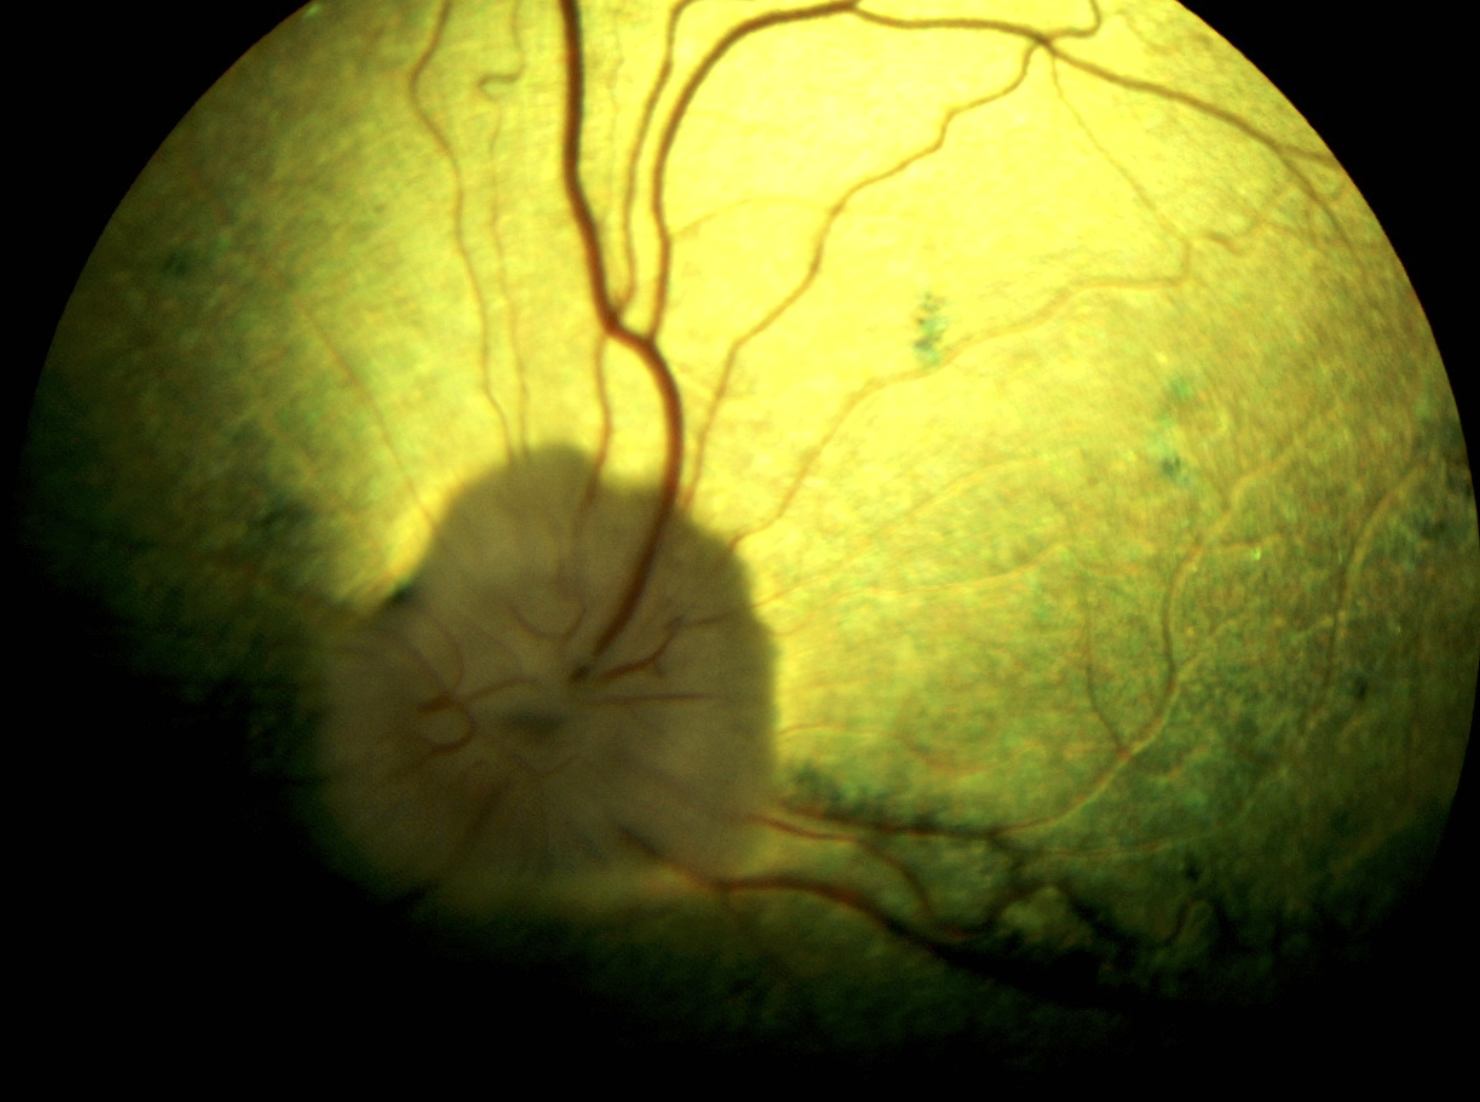

Die Progressive Retinaatrophie (PRA) stellt eine Gruppe erblicher Augenerkrankungen dar, die durch eine fortschreitende Degeneration der Netzhaut (Retina) gekennzeichnet sind und letztlich zur vollständigen Erblindung führen. Bei der Progressiven Retinaatrophie vom Typ prcd-PRA kommt es zunächst zu einer Funktionsstörung der Stäbchen, die primär für das Dämmerungs- und Kontrastsehen verantwortlich sind, was sich klinisch in einer zunehmenden Nachtblindheit sowie einer verminderten Anpassungsfähigkeit des Sehvermögens äußert. Im weiteren Krankheitsverlauf werden auch die Zapfen (Farbsehen, Sehen bei Tageslicht) in Mitleidenschaft gezogen, sodass es schließlich zur vollständigen Erblindung kommt. Die klinischen Symptome treten häufig bereits im jungen Alter auf, wobei der Zeitpunkt des Krankheitsbeginns und das Fortschreiten der Erkrankung zwischen den einzelnen Hunderassen variieren können.